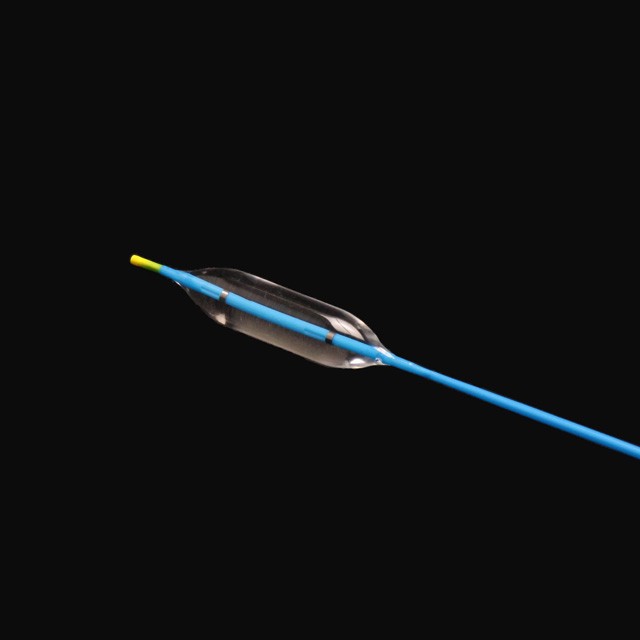

● የተጣራ ለስላሳ ጫፍ ንድፍ, ይህም በትንሽ ጉዳት ወደ target ላማው ቦታ የሚገባ .

The የቱቦው ምርጥ የቱቦው ተስማሚ ንድፍ ለስላሳ እና ጥሩ የመለጠጥ ችሎታ, ጠንካራ የመቋቋም ችሎታ እና ቀላል አለባበስ .